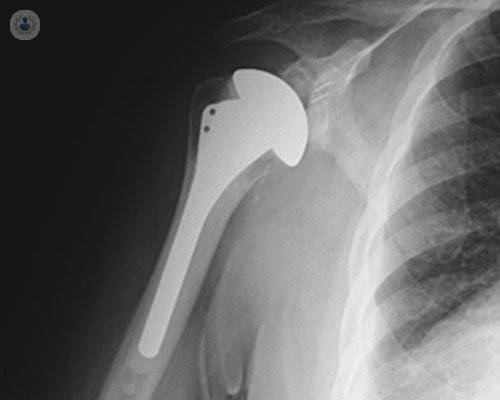

Prótesis de hombro: 4 puntos clave

El Dr. Cárdenas Clemente, especialista en Traumatología, te explica en qué casos se utilizan las prótesis de hombro, qué tipos existen, cómo se colocan y consejos para llevar un buen postoperatorio.

¿Qué debo saber sobre la cirugía de prótesis de hombro?

En ocasiones, como consecuencia de una artrosis, de una artritis o una fractura en el hombro es necesario someterse a una cirugía de prótesis. Conoce de la mano del Dr. Valdés Casas en qué consiste esta cirugía efectiva y qué tipos de prótesis existen en función del paciente.